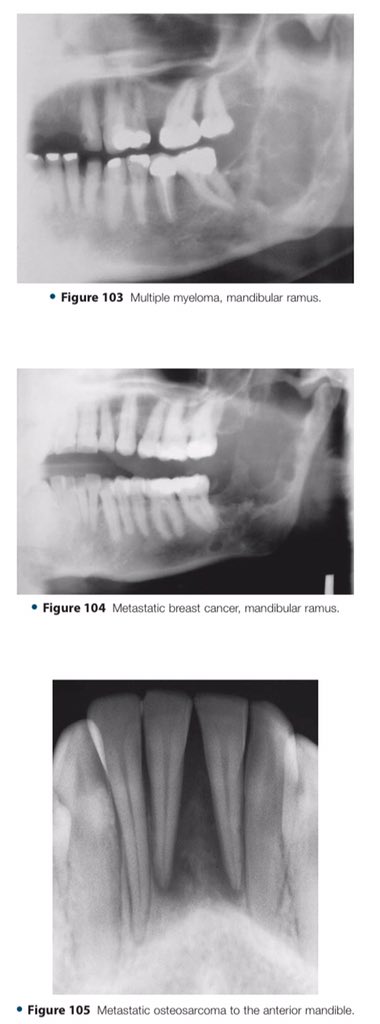

🔍| Differential Diagnosis Approach to Jaw Lesions. #aboutDent